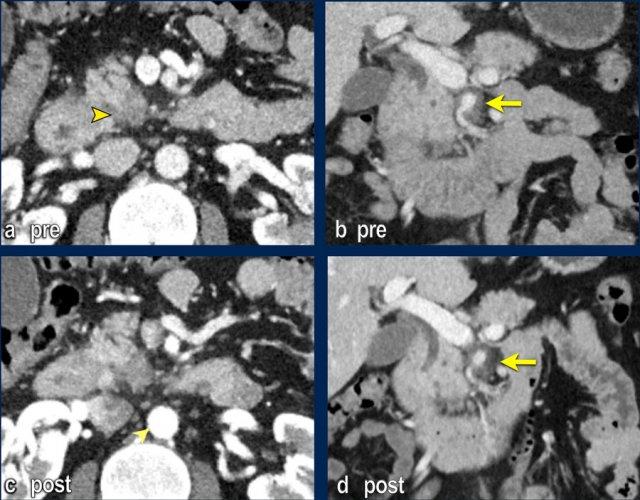

Bất thường bờ viền mạch máu

CT axial cho thấy:

- Khối u ở thân tụy (đầu mũi tên trắng).

- Tiếp xúc khu trú < 90º với động mạch mạc treo tràng trên (SMA).

- Tiếp xúc rộng hơn từ 90º – 180º với SMV, SMV bị hẹp nhẹ và biến dạng (mũi tên vàng).

- Giãn ống tụy

Tái tạo mặt phẳng coronal cho thấy:

- Bất thường bờ viền thành SMV được nhận thấy rõ hơn trên tái tạo coronal này (mũi tên).

- Huyết khối trong các nhánh bên của SMV (mũi tên xanh nhỏ).